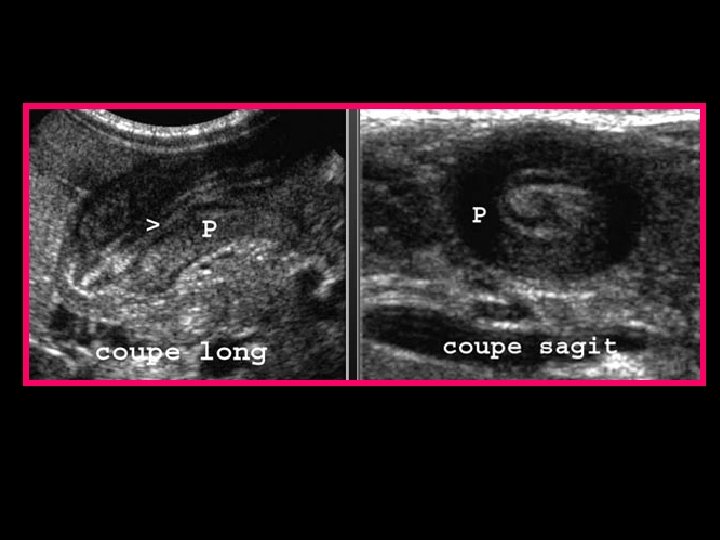

ECHOGRAPHIE ABDOMINALE • Maître examen +++ • Diagnostic précoce • Confirme le diagnostic : - longueur du pylore > 19 mm - largeur > 13 mm - épaisseur de la paroi musculaire > 4 mm • Image en cocarde en coupe transversale et en sandwich en longitudinale